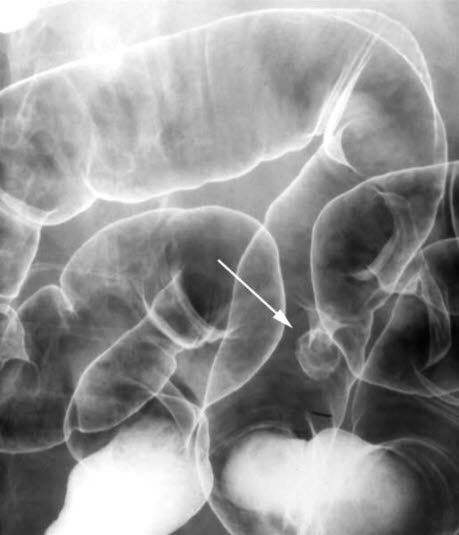

Dobbelkontrastbilde som viser en ca. 15 mm stor stilket polypp (pil) i midtre del av sigmoideum.